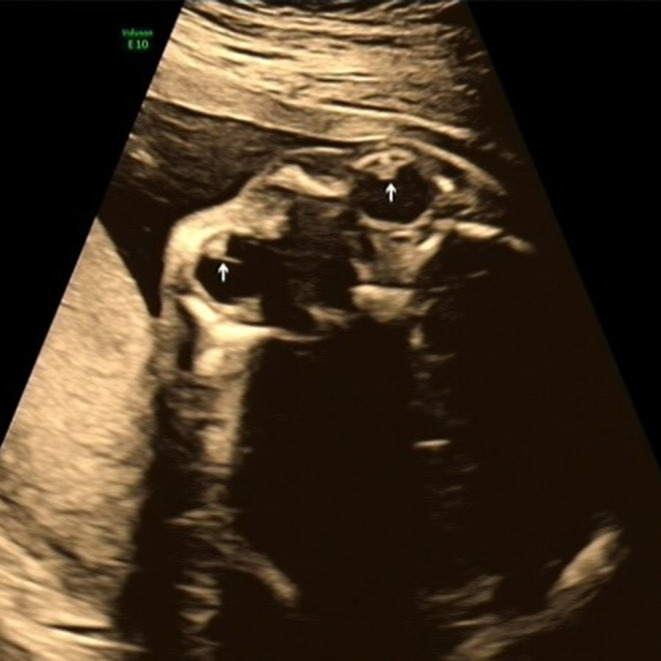

Results: Among the 29 cases, 18 (62.1%) showed complete hyperechogenicity of the lens (type I), 6 (20.7%) showed dot or cluster hyperechogenicity within the lens (type II), and 5 (17.2%) showed the "double-ring" sign (type III). Moreover 18 (62.1%) involved isolated cataract and 11 (37.9%) involved cataract associated with extraocular abnormalities, with central nervous system and cardiac abnormalities being the most common. In terms of potential etiology, five cases (17.2%) had a family history, and genetic testing was performed in eight cases, with five of them showing abnormalities. Cases 2 and 16 involved two fetuses of the same pregnant woman, both of which had a hemizygous mutation of the OCRL gene (c.1514G > A). Moreover Case 3 involved Trisomy 13, and Case 17 had heterozygous mutations of the RAB3GAP1 gene (c.718C > T and c.1879dupA). Furthermore, Case 21 had a heterozygous mutation of the NHS gene (c.375C > A). Among the 29 cases, pregnancy was terminated in 21 (72.4%) and was continued in 4 (13.8%).

Conclusion: Congenital cataract, defined as lens opacity, presents as complete hyperechogenicity of the lens, a double-ring sign, or dot and cluster hyperechogenicity within the lens on prenatal ultrasound. Prenatal ultrasound can help assess the eyes and other systems during prenatal or postnatal examinations and can provide additional information for prenatal counseling and early postnatal treatment of congenital cataract.